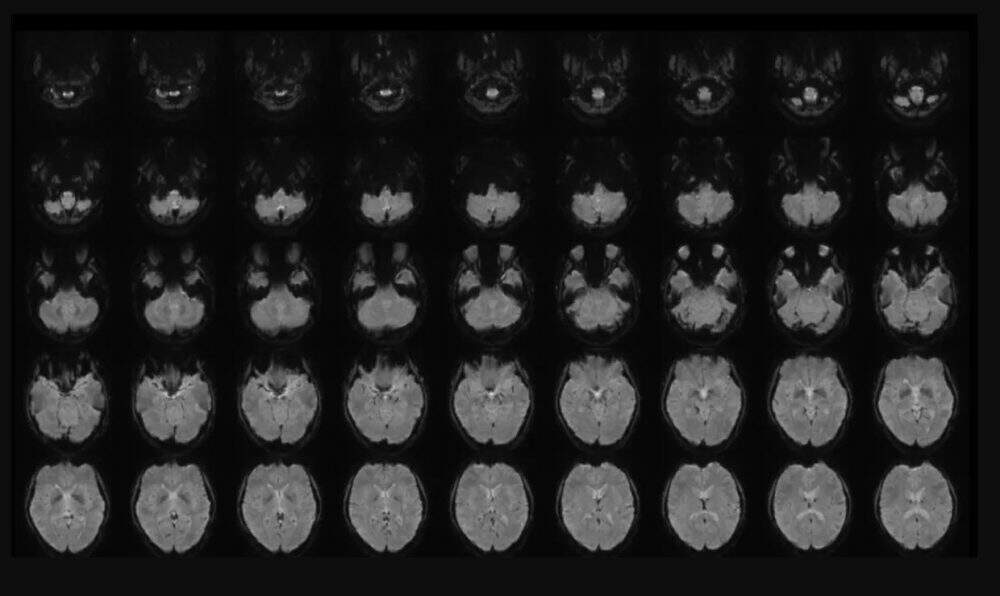

Horikawa, pesquisador dos Laboratórios de Ciência da Comunicação da empresa de telecomunicações NTT, nos arredores de Tóquio, começou analisando a atividade cerebral de quatro homens e duas mulheres, falantes nativos de japonês entre 22 e 37 anos, escaneando seus cérebros enquanto assistiam a videoclipes. Os participantes visualizaram 2.180 vídeos sem som que duravam segundos e variavam em conteúdo entre objetos, cenas e ações.